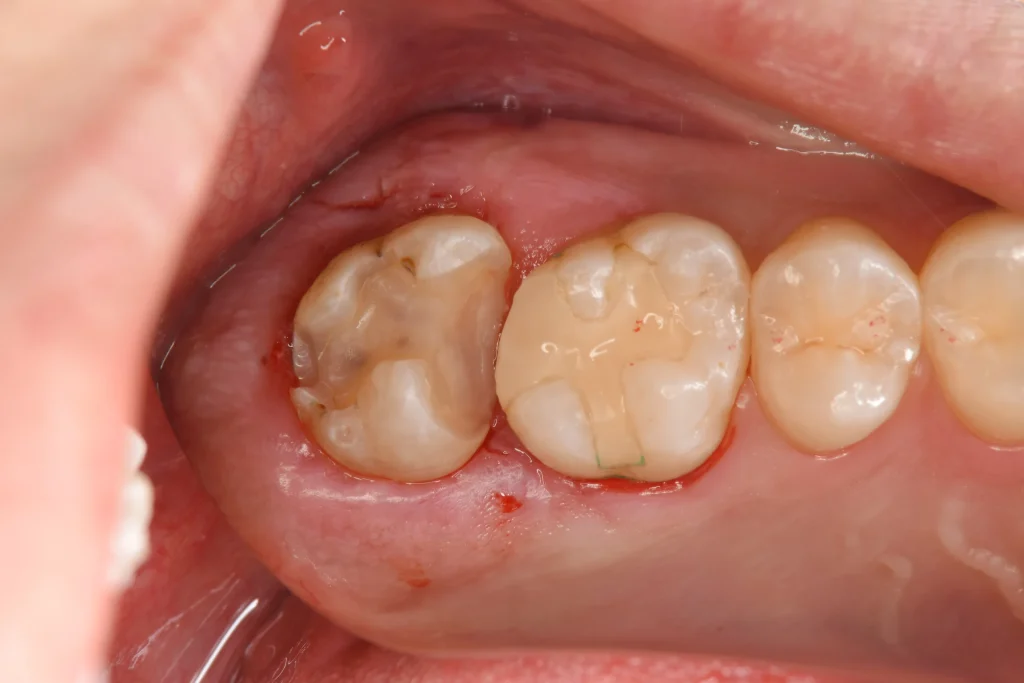

赤い点で、事前に噛む場所を確認しています。虫歯以外の場所で噛んでいないようならe-max治療は行えないためです。

赤丸で囲んだ部位が、カリエスチェッカーにて虫歯を青く染め上げた部分です。かなり大きな虫歯が隠れていたことが再確認できました。

虫歯だけを丁寧に除去後、e-maxのはまる形に修正していきます。

型取り前です。